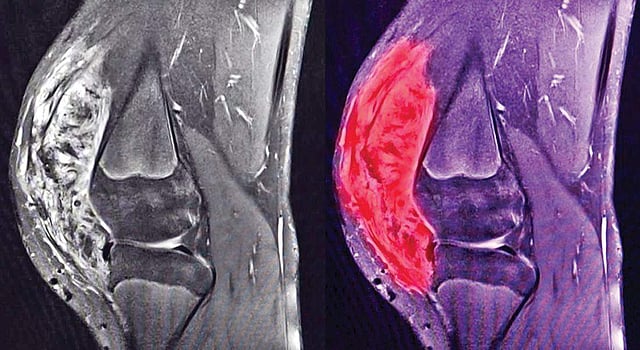

By and large, sarcomas are much rarer that carcinomas and constitute less than 1% of all cancers seen in the adults. However, it is much more common in the children and youth where it constitutes 20% of all cancers.  Since the connective tissues are present everywhere in the body, it can occur at any place, but is more commonly seen in arms, legs and trunk. Depending upon the tissue of origin, these sarcomas can be of various types such as bones – osteosarcoma, muscles- leiomyosarcoma, fat – liposarcoma, blood vessels – angiosarcoma, lymph vessels – lymphangiosarcoma etc. They all look different under the microscope and different type of sarcoma may need different treatment.

Often, various other tests such as Immunohistochemistry and Molecular profilling are required to obtain the correct diagnosis. A CT Scan, MRI scan or PET CT scan may also be required to ascertain the characteristics of the tumour and the extent of spread. The main treatment modalities are surgery, radiotherapy, chemotherapy and targeted therapy. Sometimes a combination of these treatment are required depending upon the nature and stage of sarcoma. Sarcoma diagnosed in early stages are generally curable, but not so in advanced stages. Limb preservation surgeries are generally attempted and have become standard practise wherever possible. In advanced stages chemotherapy and targeted therapies are the mainstay on treatment.